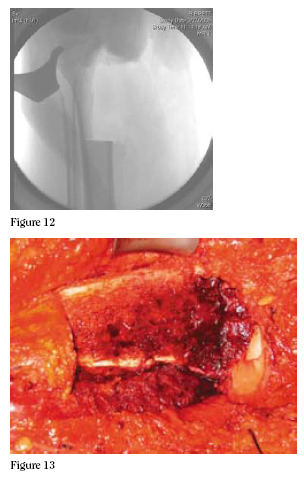

flap. Then, using C-arm control, K-wires were placed outlining

the length and extent of our osteotomy. (Figures 10 and

11) An oscillating saw and osteotomes were used to make the

osteotomy. We had direct visualization of the articular surface

at this point and placed the osteotome just medial to the tibial

spines, preserving the insertion of the cruciates by undercutting

of the tibial spines. The osteotomies were completed, the

specimen was passed off, and curettings were taken for a deep

margin. (Figures 12 and 13)